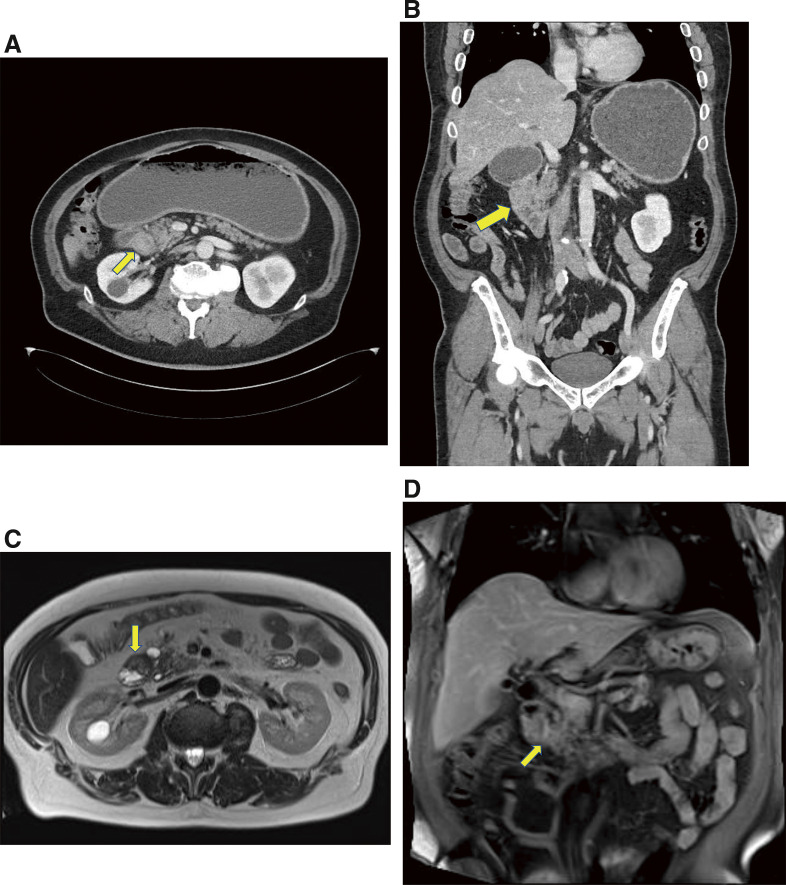

Case presentation: A 53-year-old man was admitted with abdominal distension and recurrent vomiting. Esophagogastroduodenoscopy revealed a complete duodenal obstruction without malignant findings. Computed tomography revealed wall thickening in the second portion of the duodenum. The common bile duct and main pancreatic duct were not dilated. As there was no evidence of malignancy, we performed gastrojejunostomy as a bypass to improve the symptoms. Five months later, follow-up blood examinations showed elevated total bilirubin levels, and computed tomography revealed persistent thickening of the duodenal wall with exacerbated dilation of common bile duct and main pancreatic duct. Mucosal biopsies from the oral and anal sides of the stenosis revealed no malignancy. Due to a strong suspicion of malignant disease and difficulty in preoperative biliary drainage, we performed pancreatoduodenectomy. Pathological examination revealed mucinous adenocarcinoma with submucosal and subserosal invasion of the duodenum. We finally diagnosed this case as ampullary carcinoma.